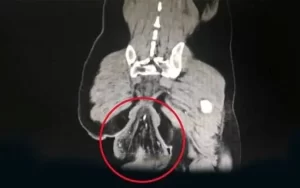

O diagnóstico foi de prolapso retal, uma condição rara e grave em que a parte final do intestino grosso perde sua sustentação